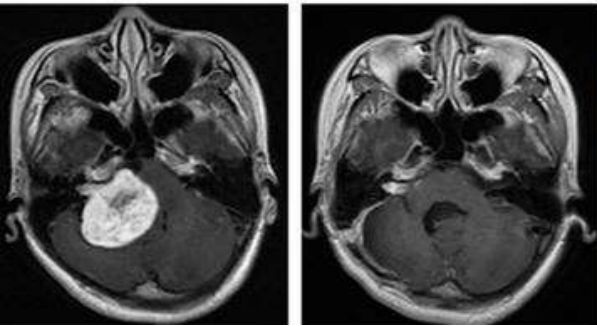

B、对于眼癌的患者,质子治疗可以在避免眼球摘除手术的前提下达到相同的治疗效果。美国麻省总医院治疗儿童视网膜母细胞瘤的质子治疗计划,很清楚地看到质子治疗病灶周边非常干净,没有多余的射线残留,而传统放疗波及范围就很大了,对于眼睛这一重要器官,治疗时尤其要注意并且要尽最大努力进行保护,质子治疗有绝对的优势。而放疗相关的或原位出现的第二恶性肿瘤的10年发病率有显著差异(质子vs光子:0%vs14%)